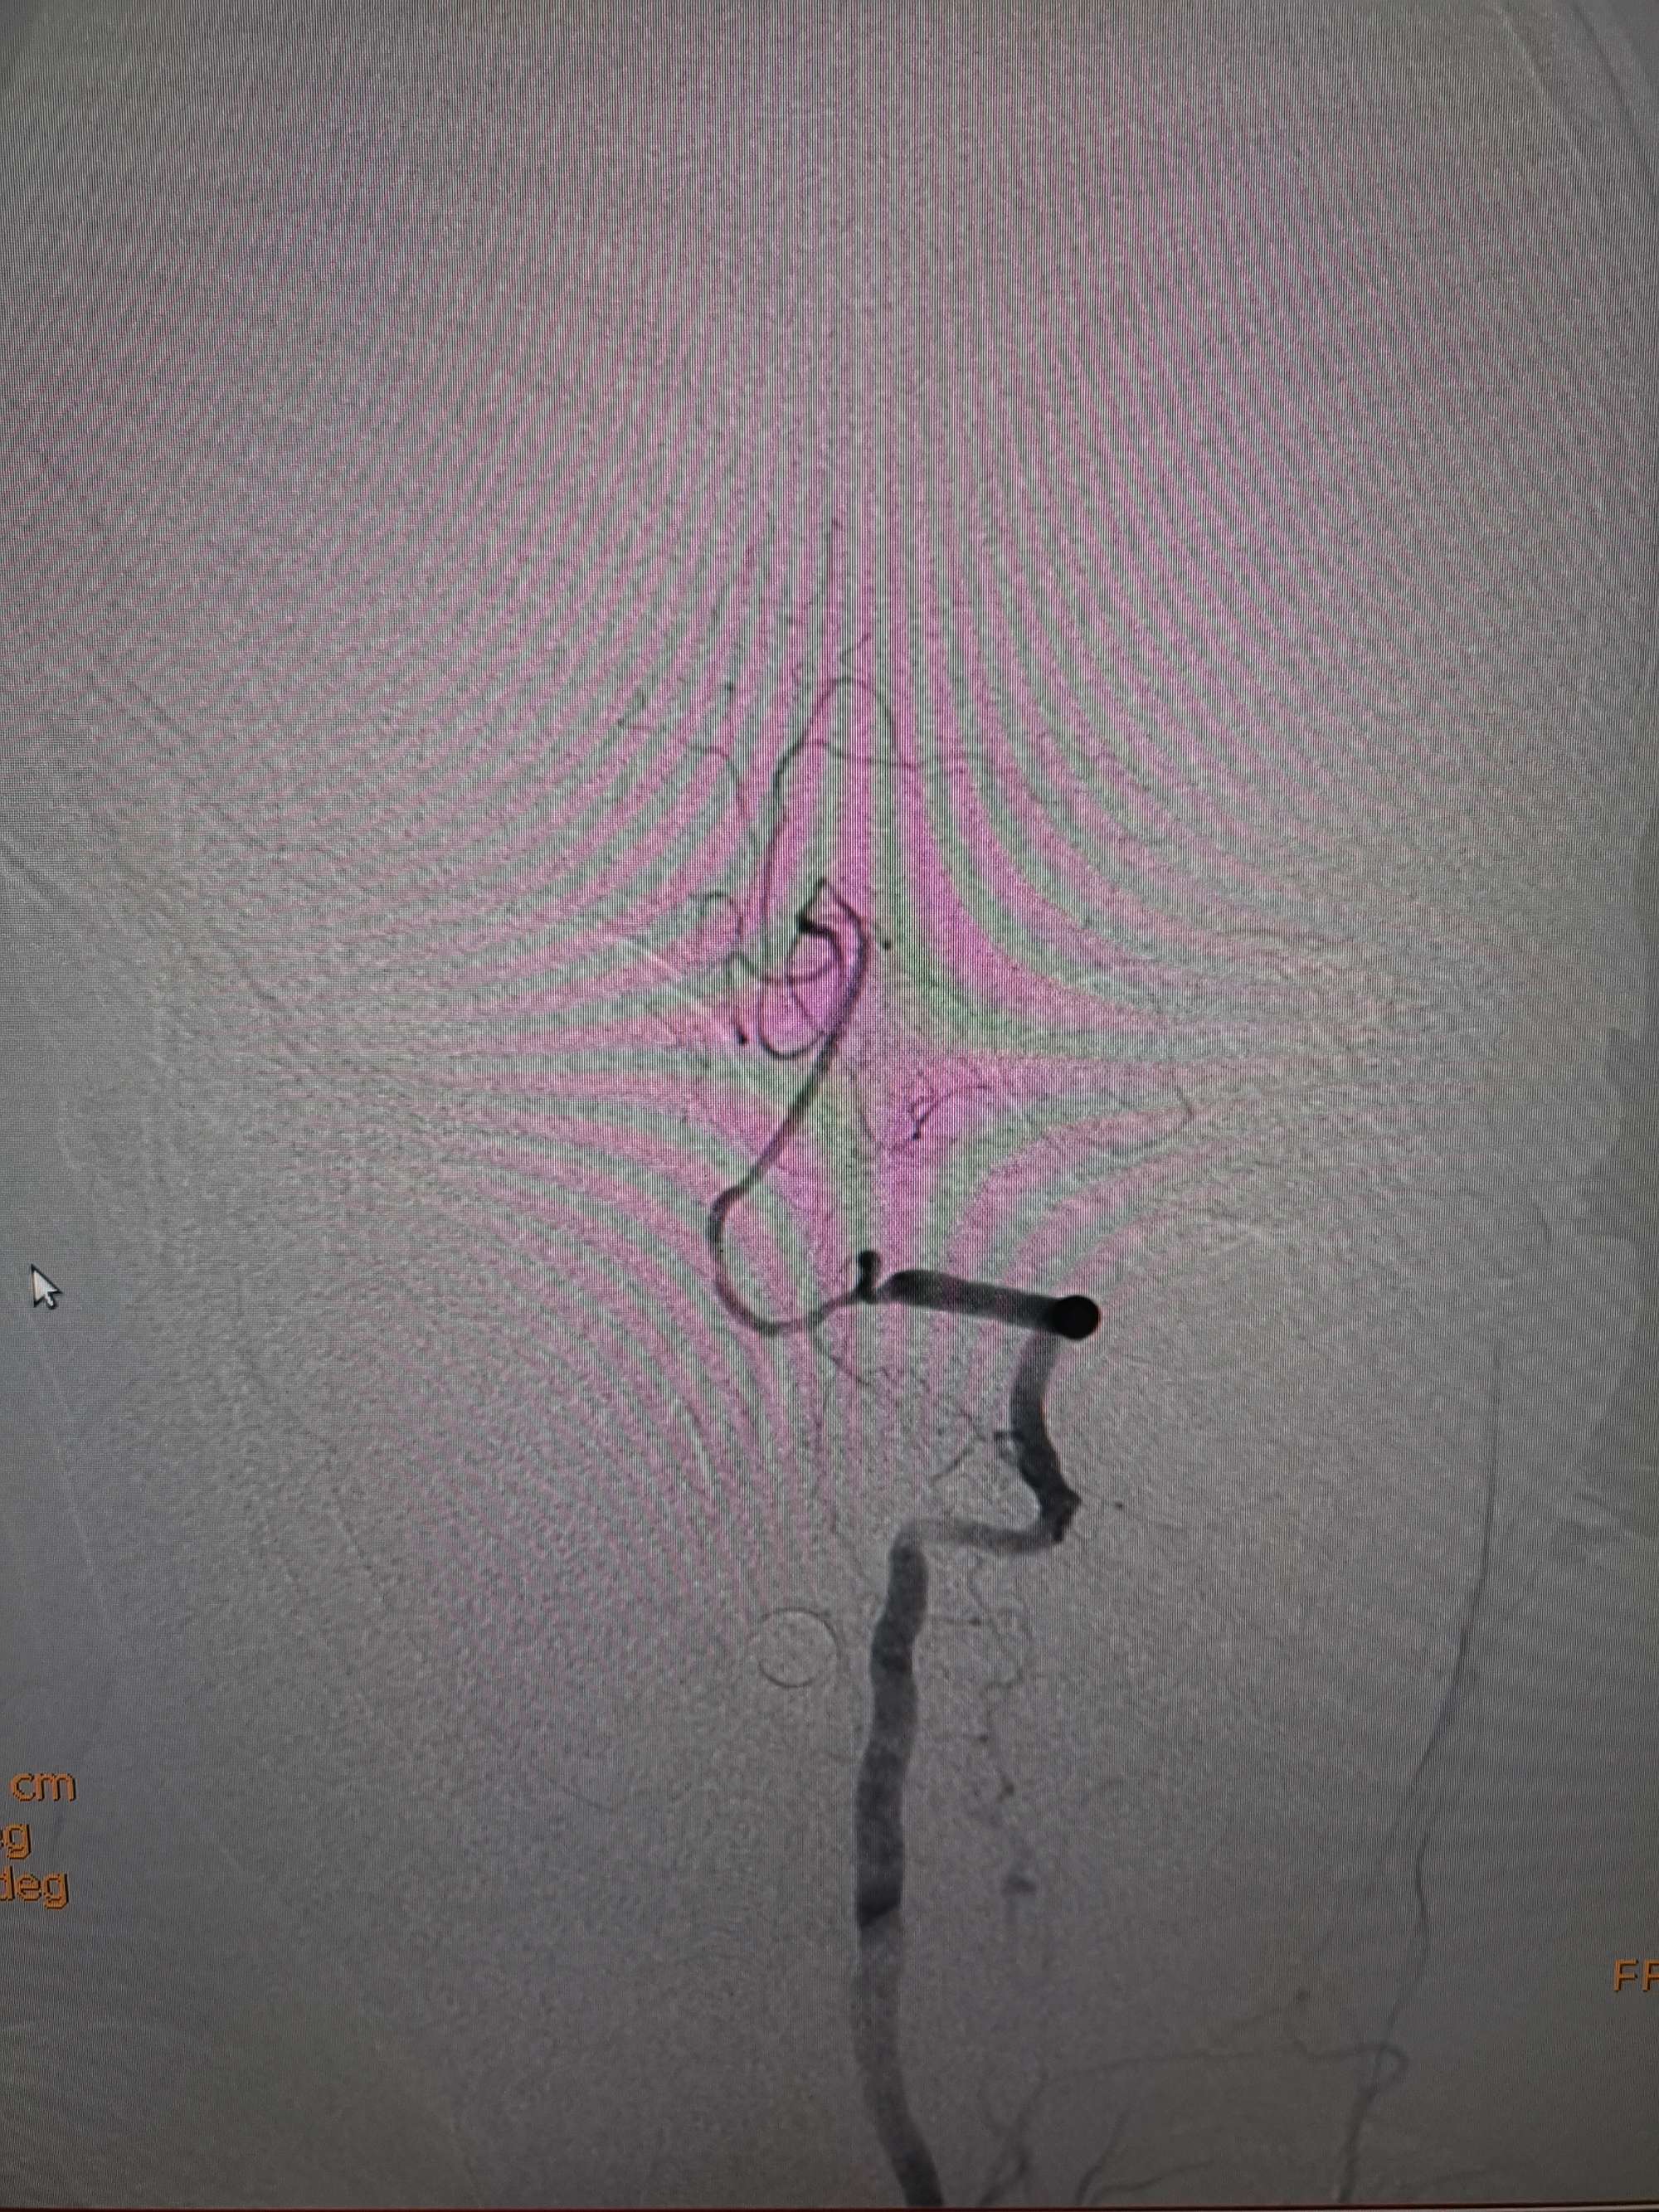

手术过程

在微导管支撑下先将微导丝和微导管穿过闭塞段,微导管超选造影证实位于基底动脉真腔后更换300cm外周交换导丝,撤出微导管后按从小到大,从远到近的原则行球囊扩张,本例手术选择了1.5✖️15、2.0✖️20、2.5✖️20球囊进行扩张,扩张满意后植入Enterprise支架,手术结束。

术后造影见左侧椎动脉闭塞段管腔恢复正常直径,远端血运良好。